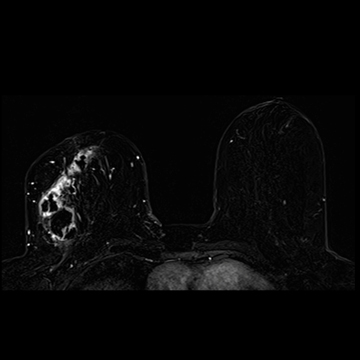

乳腺

MRI画像(提供:シーメンスジャパン株式会社)